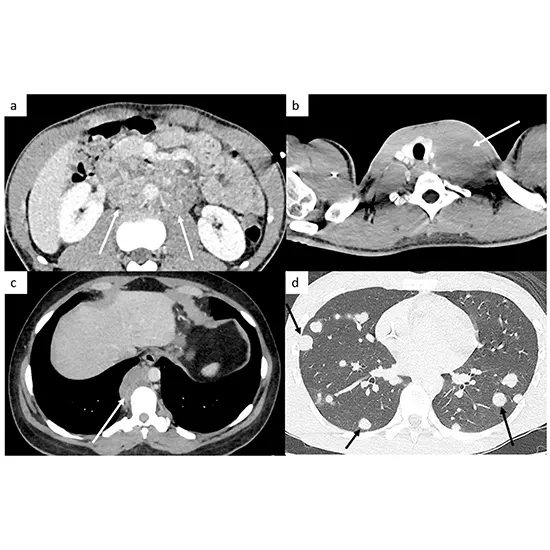

CT (computed tomography) imaging is essential for providing cancer patients with ongoing care. Patients often have routine CT scans after receiving a cancer diagnosis and treatment to check for any potential cancer recurrence or disease progression.

To check for probable cancer development or recurrence, cancer patients receiving follow-up care may have CT imaging.

Doctors can spot any changes in tumors or other tissues because of the precise images of the body's internal components that CT scans reveal.

The size, shape, position, and characteristics of any tumors or lesions present can be learned via CT scans, which also can detect tumors that are too small to be felt during a physical examination.

By demonstrating whether tumors have decreased or grown in response to treatment, CT scans can be used to evaluate the efficacy of cancer treatment.